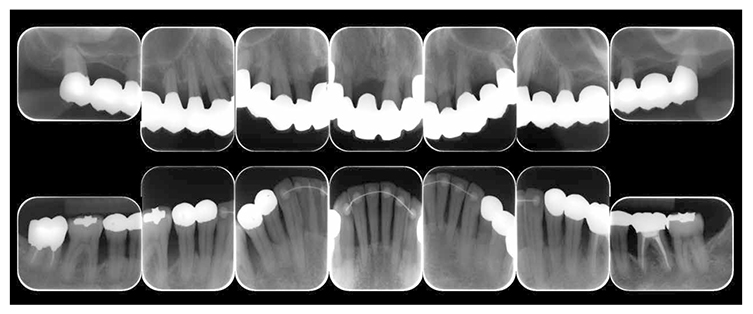

(3) X-ray findings

At the first visit, the findings showed moderate to advanced horizontal alveolar bone resorption in the entire jaw, and advanced vertical bone resorption on 24,36,46, 47. Additionally, on 46,47 were radiolucent findings that were likely associated with furcation involvement, and radiolucent areas on the alveolar bone surrounding the root apex were shown on 16,11,26. Furthermore, distally on 47, radiolucent findings showed caries extending into the dental pulp.(Fig.1c).

(Fig.1c) Dental X-ray 14 during first visit (June 2007)